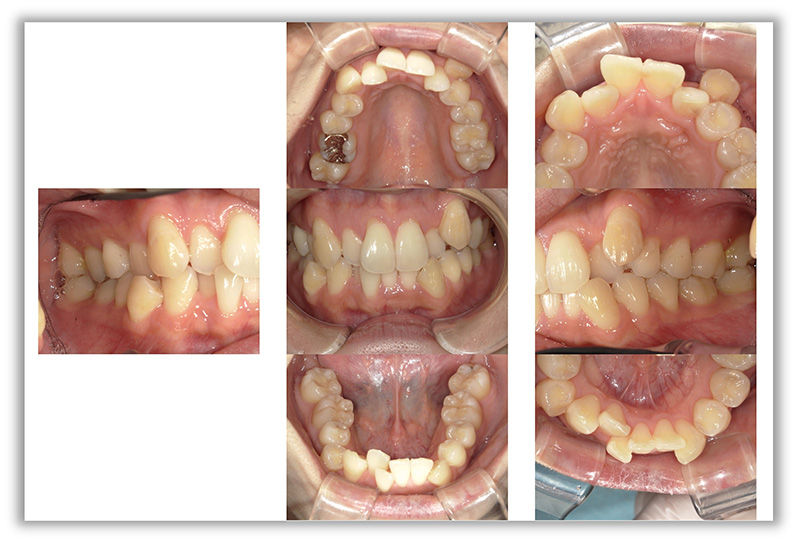

CASE_01

40代男性(インビザライン矯正+セラミック治療)

- 患者さん情報(年齢・性別)

- 40代 男性

- 主訴

- 歯並び、銀歯を白くしたい

- 治療箇所

- 10か所

- 治療方法

- 銀歯をセラミックに変更

- 費用

- インビザライン77万円

- セラミック10か所約80万円

- 治療期間

- インビザライン約1年

- セラミック治療10か所約8か月

- その治療によるリスク・副作用

- 歯肉退縮することがある

- 矯正中はしみたり、痛みを伴うことがある